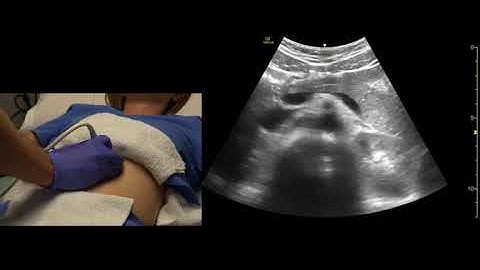

How to Scan the Pancreas